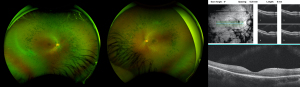

Case 2 is now a 28-year-old Hispanic male sibling of Case 1, with history of decrease in night vision starting at age 5 years old and seizures starting at age 16 years as previously reported. Molecular testing revealed the same variants as his affected sibling on the CLN8 gene. At age 22 years his visual acuity was OD 20/25 and OS 20/30 which remained unchanged at age 28 years. Fundus exam originally revealed pallor of optic nerves, attenuated vasculature, peripheral bone spicules and diffuse retinal pigment epithelial mottling. On recent follow up, fundus examination and ultrawide field color fundus imaging showed mid-peripheral bone spicules and mild attenuation of vasculature (Figure 7). OCT showed no CME and fundus autofluorescence showed scattered macular areas of decreased and increased intensity. Since the initial report he has had one witnessed generalized tonic clonic seizure lasting less than one minute in the setting of weaning of his anti-epileptic medication which has since been adjusted.

Descriptions of the ophthalmic findings from routine ophthalmologic examination are provided for the sibling pair of CLN8 patients. Retinal imaging was acquired, including ultrawide field color fundus imaging (Optos, United Kingdom) and spectral domain OCT (Zeiss Cirrus instrument, Germany).